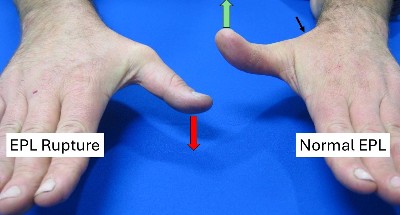

- It allows you extend your thumb and lift it up when your hand is palm downward.

- If the EPL ruptures the thumb droops down.

- Pain & swelling on back of the wrist with thumb extension

- Sudden Inability to lift the thumb up (extend the thumb) without warning.

- Pain settles after the rupture